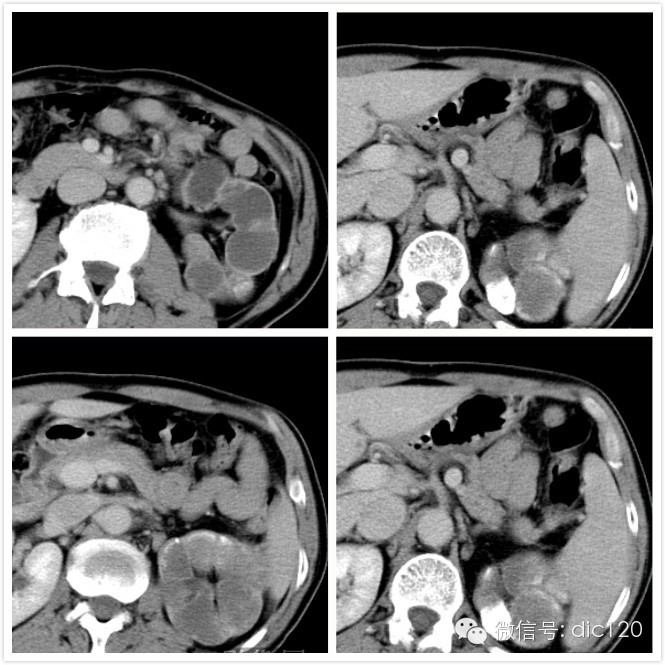

CT增强肾皮质期图像

CT图像特点:左侧肾盏、肾盂扩张,呈多发囊性低密度灶,囊内CT值略高于水;肾脏实质萎缩。 病变内可见结节状、云絮样子钙化灶,增强后未见明显强化。

CT:① 早期显示肾实质内多发形态不规则低密度灶,边缘不规整,可与肾盂肾盏相通,增强扫描病灶区无明显强化;

② 病变进展,可见部分肾盏或全部肾盏、肾盂扩张,呈多发囊性低密度灶,囊内CT值略高于水;

③ 病变内可见大小不一钙化灶,呈点状或不规则高密度影,严重者肾大部或全部弥漫性钙化。